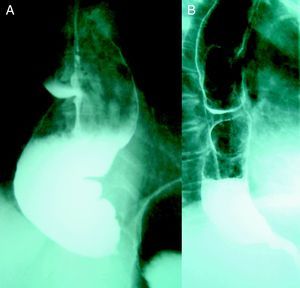

Parece que el éxito de la miotomía de Heller puede verse comprometido en casos de larga evolución con dilatación esofágica superior a los 4cm, señalando algunos autores incluso la esofaguectomía como primera opción terapéutica. En nuestra experiencia sin embargo, en pacientes con esófago sigmoideo se han obtenido buenos resultados tras la cardiomiotomía (fig. 3). Valorando además la importante morbimortalidad asociada a la esofaguectomía consideramos de primera elección la intervención de Heller independientemente del grado de dilatación esofágica.